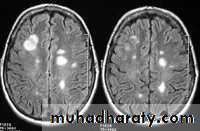

MULTIPLE SCLEROSIS:

-common neurological disorder.

-characterized by disseminated plaques of demyelination & gliosis throughout the neuraxis.

-the sites of election are:

1.periventricular.

2.optic pathways.

3.brainstem.

4.cerebellar white matter & peduncles.

5.spinal cord.

-young adults are primarily affected.

-MRI is more sensitive than CT in the demonstration of MS plaques.

- the most characteristic appearance is that of peri ventricular nodular Hyper intense lesions on T2 weighted images.

-the plaques are also well seen at the gray- white matter interfaces.

-MRI can even image lesions in the spinal cord , brainstem & cerebellum.

-multiple cerebral lesions are seen in over half the patient presenting with a single episode of optic neuritis.

-some lesion may show a central area of greater signal intensity , resembling a target.

-contrast enhancement after giving gadolinium occurs in the acute phase indicating activity & in the chronic phase doesn't enhance.

-differential diagnosis :1-ischaemic lesions ,2-following radiotherapy , 3- in encephalomyelitis.

MRI

SAGITAL FLUID ATTENUATION INVERSION RECOVERY SEQUENCE: OVOID PLAQUES ( HIGH SIGNAL INTENSITY) , WHICH ARE PERPENDICULAR TO LATERAL VENTRICLE.